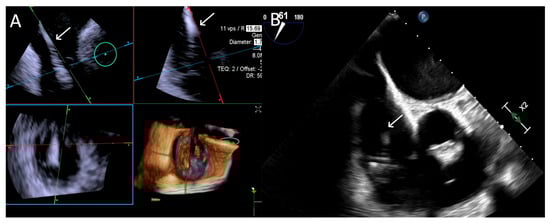

- Step number 1: assessment of tricuspid valve anatomy.

- -

- Step number 2: identification of the target lesion.